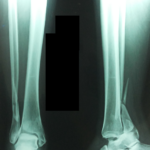

Posterior Malleolus Fracture with Dislocation

A 38 year old presents to the Emergency Dept with a history of significant trauma to the ankle , there is minimal swelling, deformity is present, there is only minimal soft tissue injury(Tscherne grade 1), and no signs of distal ischemia. She has been admitted within 3 hours after injury. There are no comorbidities. What […]